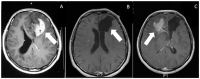

Glioblastoma is the most common and malignant primary brain tumor, defined by its highly aggressive nature. Despite the advances in diagnostic and surgical techniques, and the development of novel therapies in the last decade, the prognosis for glioblastoma is still extremely poor. One major factor for the failure of existing therapeutic approaches is the highly invasive nature of glioblastomas. The extreme infiltrating capacity of tumor cells into the brain parenchyma makes complete surgical removal difficult; glioblastomas almost inevitably recur in a more therapy-resistant state, sometimes at distant sites in the brain. Therefore, there are major efforts to understand the molecular mechanisms underpinning glioblastoma invasion; however, there is no approved therapy directed against the invasive phenotype as of now. Here, we review the major molecular mechanisms of glioblastoma cell invasion, including the routes followed by glioblastoma cells, the interaction of tumor cells within the brain environment and the extracellular matrix components, and the roles of tumor cell adhesion and extracellular matrix remodeling. We also include a perspective of high-throughput approaches utilized to discover novel players for invasion and clinical targeting of invasive glioblastoma cells.